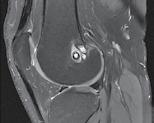

CT-ul cu reconstrucție tridimensională sau RMN genunchi relevă mult mai

bine complexitatea fracturii și dau posibilitatea unui planning preoperator superior estimării radiologice clasice(7). CT-ul este mai rapid și mai ușor de făcut, dar RMN decelează mai bine leziunile de menisc sau ligamentare.